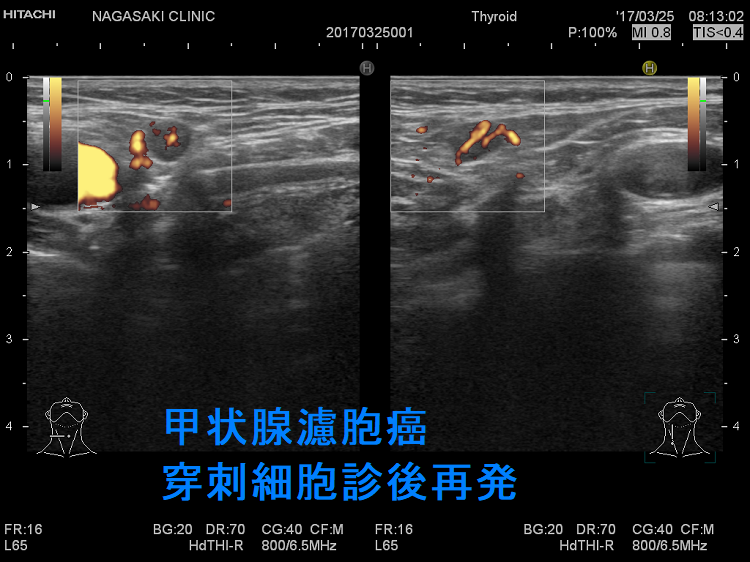

甲状腺穿刺細胞診後再発(穿刺経路再発)

甲状腺濾胞癌 穿刺細胞診後再発 超音波(エコー)画像

甲状腺濾胞癌 甲状腺穿刺細胞診後再発(穿刺経路再発) 超音波(エコー)画像

甲状腺濾胞癌 穿刺細胞診後再発 超音波(エコー)画像 ドプラーモード

甲状腺濾胞癌 甲状腺穿刺細胞診後再発(穿刺経路再発) 超音波(エコー)画像 ドプラーモード

甲状腺濾胞癌穿刺細胞診後の局所再発(甲状腺穿刺細胞診後再発、穿刺経路再発)もあり得ます。穿刺経路に残った濾胞癌細胞の増殖によります。